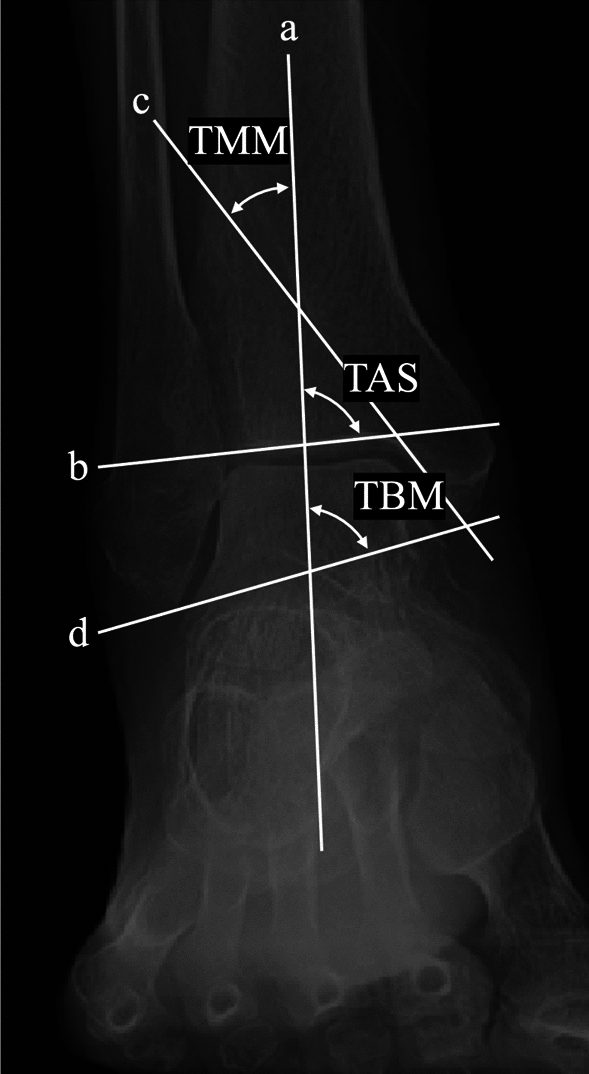

Methods: We retrospectively analyzed 331 patients who underwent unilateral mechanical alignment (MA) TKA for knee osteoarthritis. A control group of 40 healthy subjects was used to define normal alignment ranges. Whole-leg anteroposterior weight-bearing radiographs were obtained preoperatively and 2 months postoperatively. Alignment parameters included the hip-knee-ankle angle (HKA), tibiotalar tilt angle (TTA), tibial plafond inclination angle (TPIA), talar inclination angle (TIA), and hindfoot alignment angle (HAA). Pre- and postoperative values were compared using the Wilcoxon signed-rank test, and changes in the proportion of patients within the normal range were determined. Wilcoxon rank-sum tests and chi-squared tests were used for group comparisons, and multivariate logistic regression identified independent predictors of persistent malalignment.

Results: HKA improved after TKA (-12° to -2.0°), with corresponding improvements in TPIA (99° to 94°) and TIA (99° to 95°) (all p < 0.001), indicating a significant correction toward neutral alignment. The proportion of patients within normal range increased postoperatively from 16% to 85% for HKA, 26% to 67% for TPIA, 24% to 64% for TIA, and 65% to 73% for HAA. Multivariate analysis identified ankle OA (odds ratio [OR] = 6.62 for TTA), female sex (OR = 2.32 for TPIA; OR = 3.19 for TIA), and varus knee alignment (OR = 2.81 for TIA) as independent predictors of persistent malalignment.